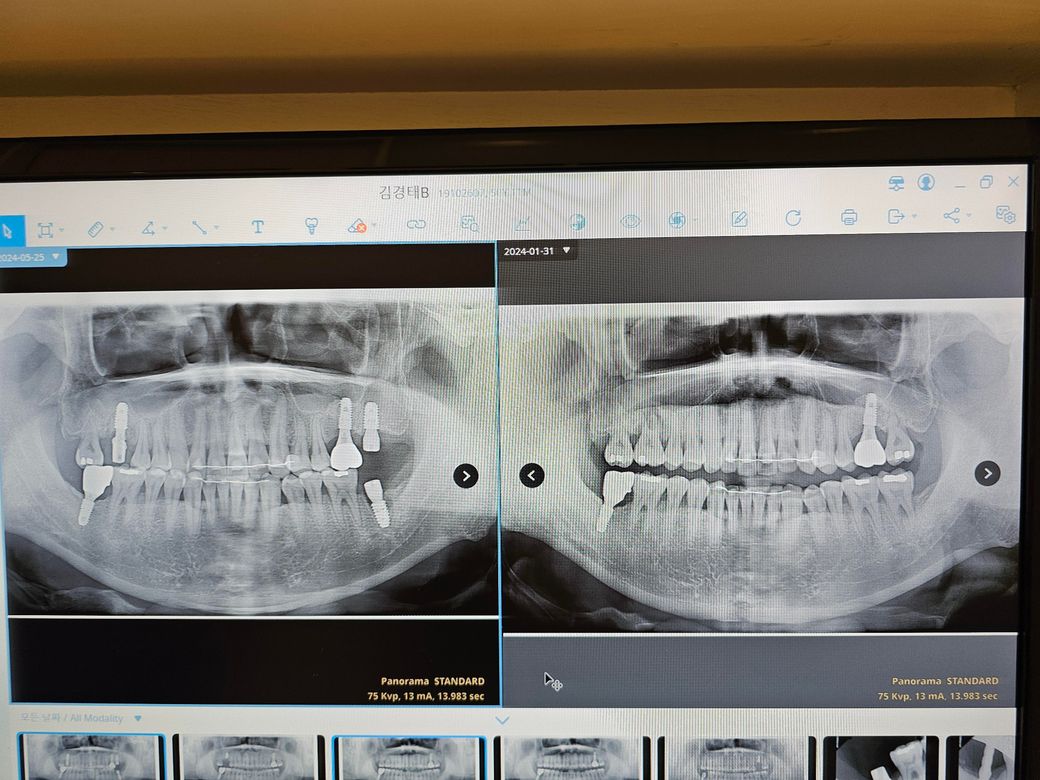

임플란트 하는중인데요 뼈이식 했는지 알수있을까요?

좌측 어금니 위 아래 뼈이식 했는지 알려주세요

윗니에 상악동거상술 해는지 알고싶어요 ...................

• 1번 째 사진

사진상 좌측에 보이는 위 임플란트 식립 시에 뼈이식이 같이 진행되어있는 것으로 보입니다.

현재 사진에서는 상악동 거상술을 했는지 정확히 알 수는 없습니다. 정확한 시술 내용을 알기 위해서는 dental-ct 등의 촬영을 해보아야 합니다. 따라서 정확한 판단을 위해서는 ct 등의 내용을 첨부해주셔야지 알 수 있습니다.

왼쪽 위에는 삼각동 부위가 고리 차 있는 것으로 보여 상악동거상술을 한 것으로 보입니다 아래 임플란트의 경우에는 골이식을 한다고 해도 해당 부위가 정확히 보이지 않는 경우도 있습니다 자세한 확인하기 위해서 치과에서 진료를 받아 보는 것을 드립니다

• 안녕하세요 치과의사 김철진입니다. 상악동 거상술을 한거 같지만 뼈이식은 햇더라도 많이 하진 않앗을것같습니다. 정확한건 치과에 문의를 해보시는게 좋을것같습니다.

• 파노라마 사진상에서는 아래쪽은 뼈이식은 안한것으로 보이고 위쪽은 상악동거상술, 뼈이식 한 것으로 보입니다만 보다 정확한 건 해당 치과에 문의하는 것입니다.